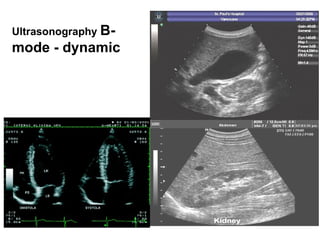

Repetitive formation of B-mode images of examined area by  fast deflection of US beam  mechanically (in the past) or electronically „in real time“ today.  Electronic probes consist of many piezoelectric transducers which are gradually activated. Ultrasonography   B-mode - dynamic

Ultrasound probes for dynamic B-mode: electronic and mechanical  (history) , sector and linear .  Ultrasonography   B-mode - dynamic Abdominal cavity is often examined by  convex probe  – a combination of a sector and linear probe.

Ultrasonography   B-mode - dynamic